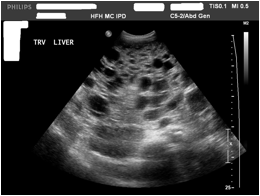

Polycystic Liver